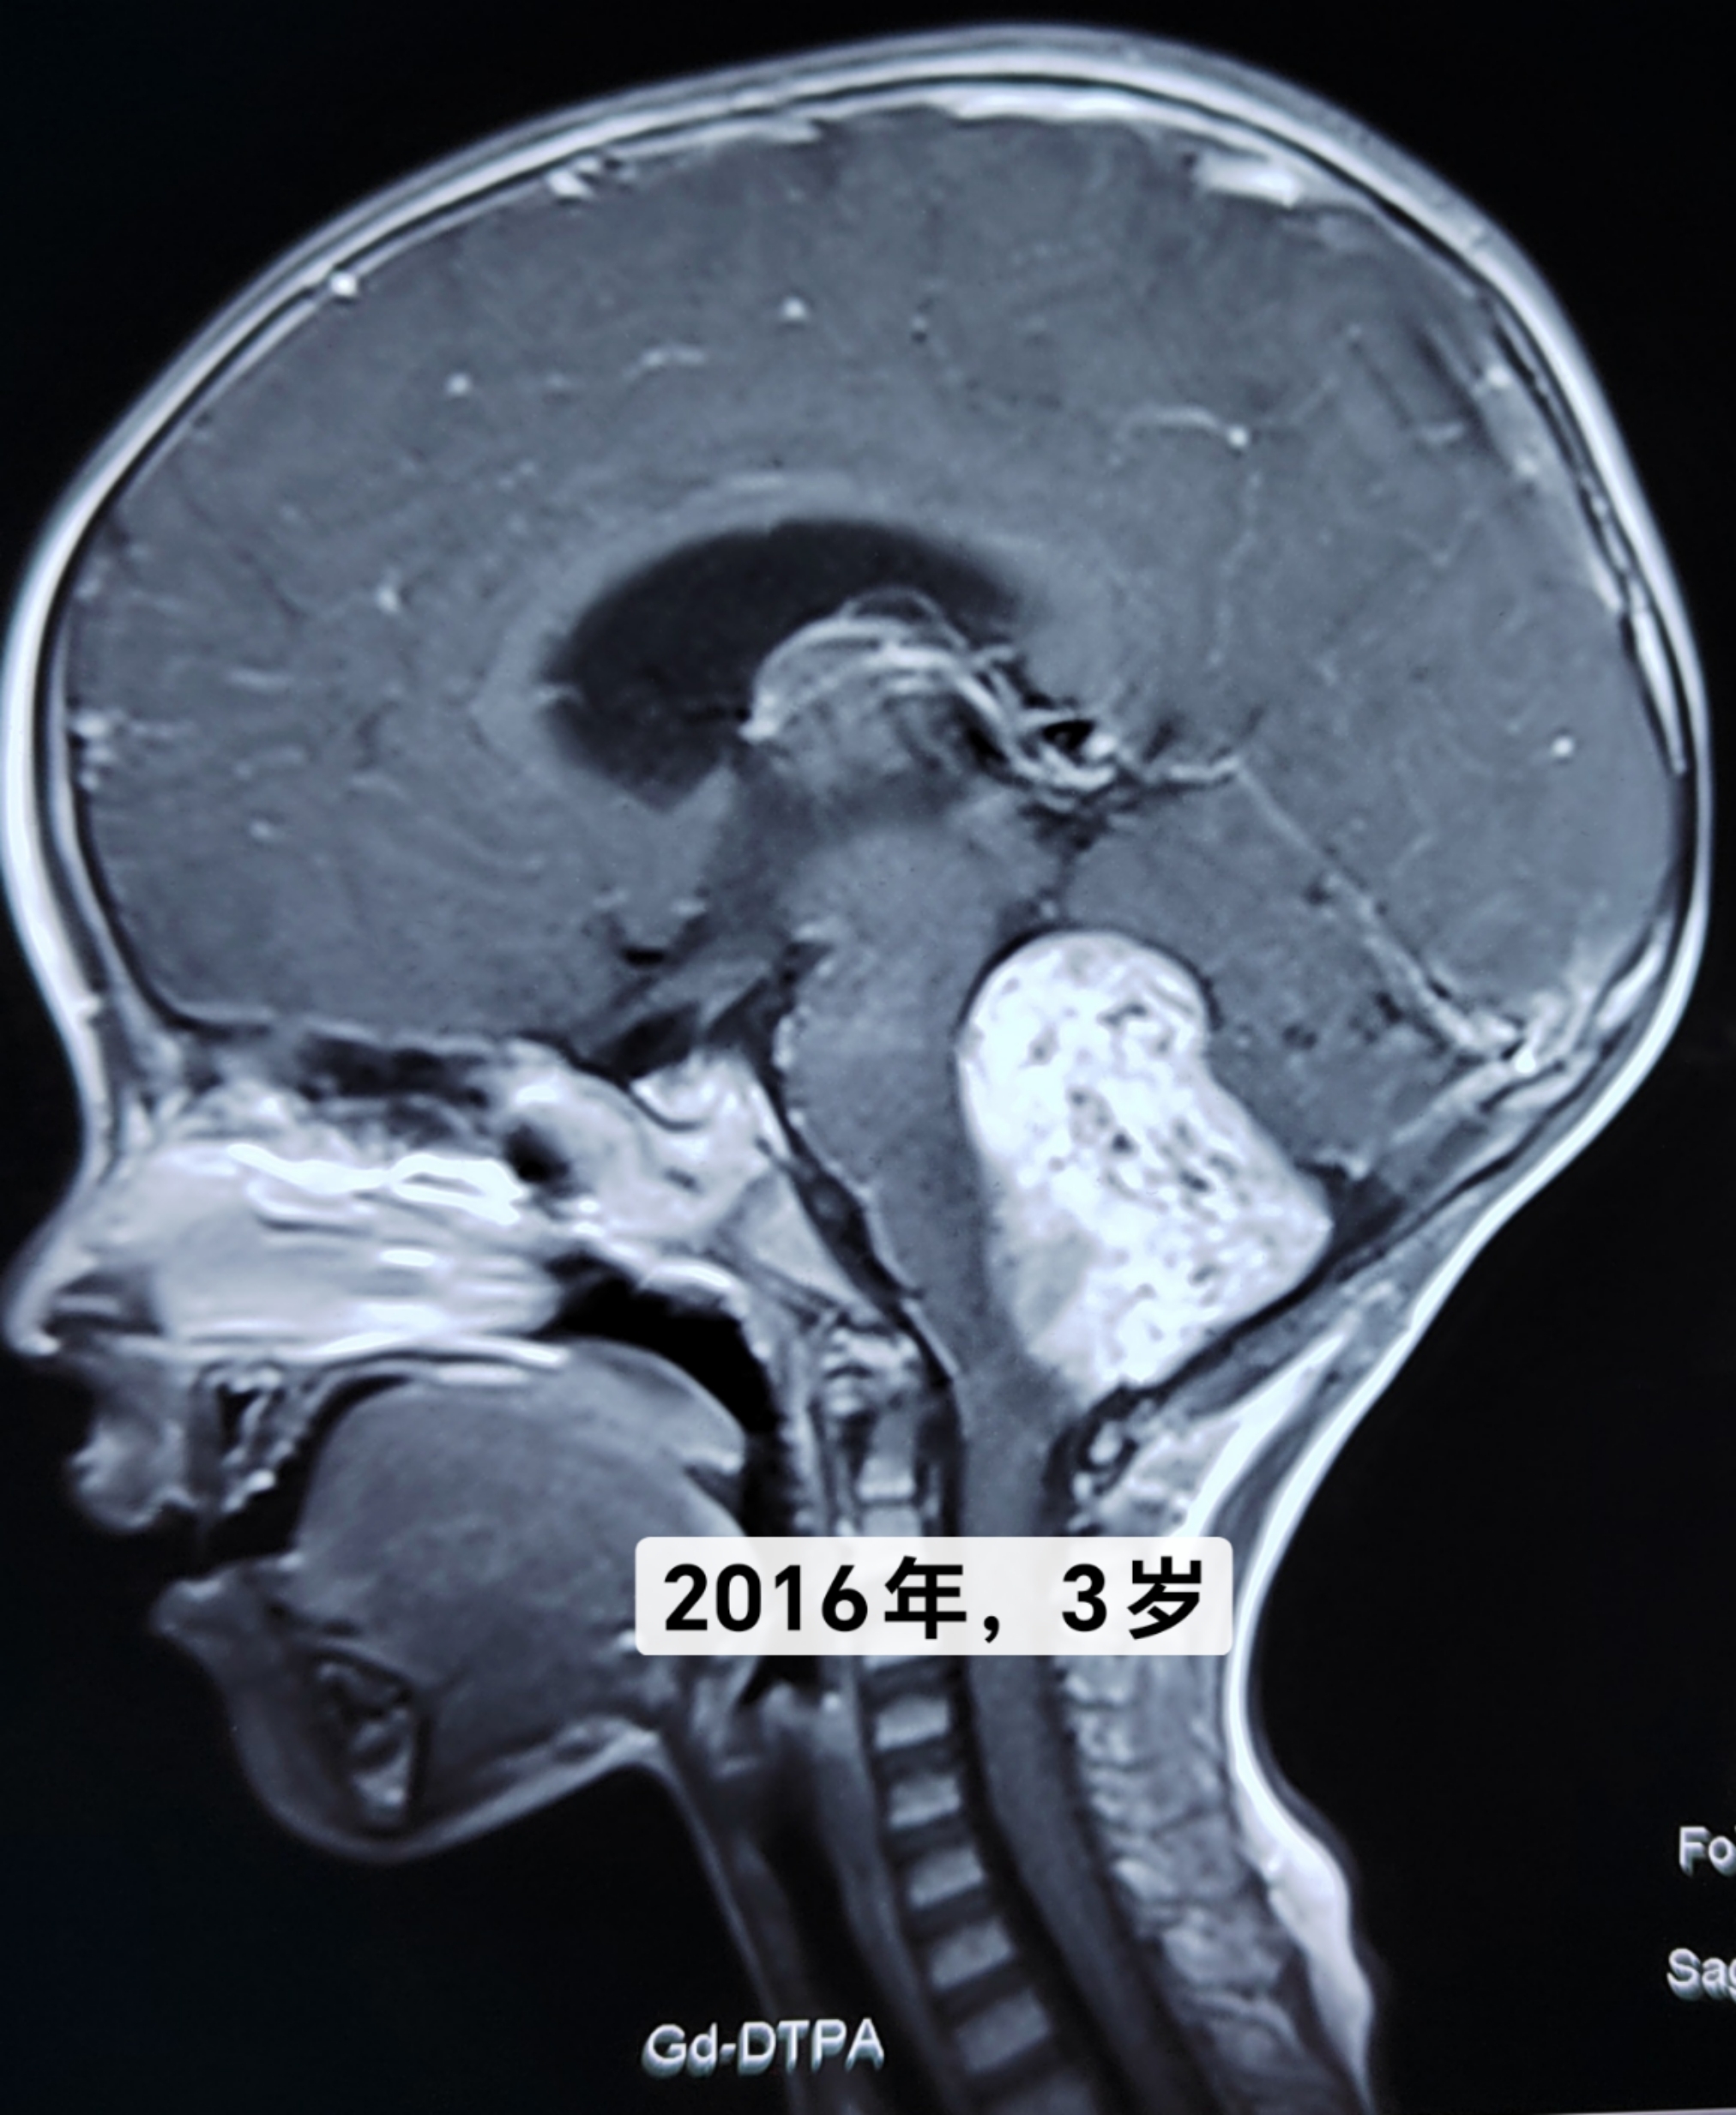

“讓子彈飛一會兒-無奈之舉”?7年前,3歲的孩子因“消瘦、發(fā)育遲緩”在外院診斷為腦干腫瘤,手術(shù)風(fēng)險極高。7年來,心大(無奈)的爸媽一直沒復(fù)查,孩子除了消瘦外癥狀不明顯。最近一周出現(xiàn)嗜睡、看東西模糊、抬不起頭。本人門診就診,復(fù)查磁共振,腫瘤較7年前長大且合并腦積水。幸運的是,這是低級別惰性(生長緩慢)生長的腫瘤,不幸的是腫瘤位于腦干。所幸手術(shù)很順利,腫瘤來源于延髓閂部,像火山一樣從腦干長出充滿四腦室。腫瘤切除滿意,閂部根基膠質(zhì)帶切除偏保守。術(shù)后肢體活動正常,無面癱、飲水嗆咳等并發(fā)癥,術(shù)后磁共振顯示腫瘤全切除,孩子順利出院,希望你能一直好運相伴[合十][合十][合十]。